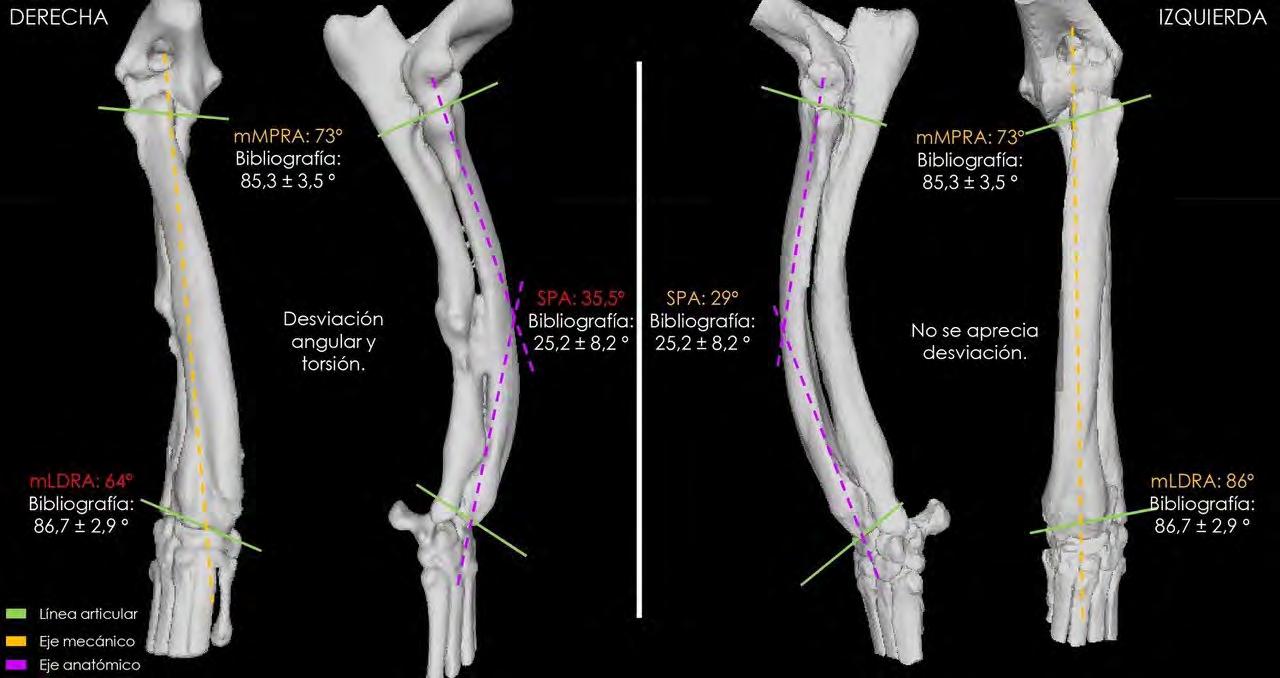

La planificación de la corrección angular se realizó apoyándonos en el estudio que, a partir de una segunda TC, hicieron los ingenieros de la empresa BETA Implants mediante la aplicación de la metodología CORA (Centro de Rotación de la Angulación) para:

En primer lugar, se llevó a cabo un estudio anatómico en el que se incluyeron tanto el radio derecho como el izquierdo. Esta metodología tiene como objetivo determinar el punto exacto (CORA) donde se debería efectuar el corte y la posterior corrección de la deformación ósea para conseguir su realineación fisiológica y biomecánica, mediante el uso de los ejes anatómicos y mecánicos, las líneas de orientación articular y los ángulos articulares.

Estas mediciones angulares nos permiten comparar el radio afectado con uno estándar y cuantificar cuánto se desvía de los valores morfológicos. Además, es clave realizar dichas mediciones también en la extremidad contralateral (Fig. 1), porque, en caso de no presentar ninguna patología o síntomas clínicos, nos permite aproximar la corrección y respetar en la medida de lo posible la distribución simétrica de cargas.3-5

Si se elucidan más ejes de los que suelen existir para el hueso en cuestión, la intersección de los ejes óseos correspondería al vértice de la deformidad (o deformidades), lo que da lugar a la identificación de un CORA. Por ejemplo, el radio canino posee un eje anatómico singular en el plano frontal. Si se examina un radio concreto utilizando el método CORA y se establece que posee dos ejes anatómicos en el plano frontal que se cruzan dentro de las corticales del hueso, entonces la intersección de los ejes definiría una deformidad singular y se consideraría una deformidad uniapical.5 En nuestro caso, el CORA quedó determinado por la intersección de dos ejes anatómicos (líneas rosas en Figs. 1 y 2). Por tanto, en este punto es donde se realizará el corte y posterior giro del fragmento distal para realinear cúbito y radio, es decir, el punto donde se efectuará la ostectomía en estos huesos que al haber quedado unidos se tratarán en bloque (Fig. 2).

Figura 1. Comparativa en 3D de ambas extremidades con la correspondiente deformidad.